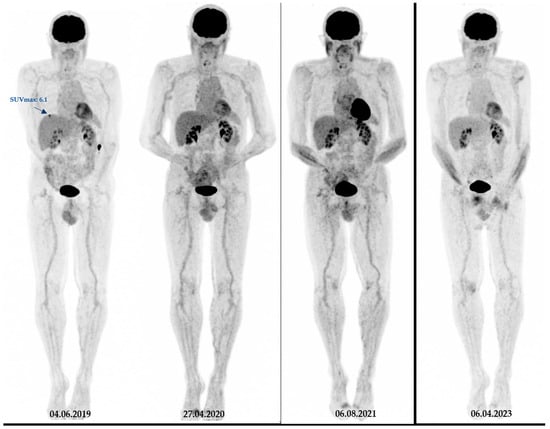

3.3. Patient Outcome